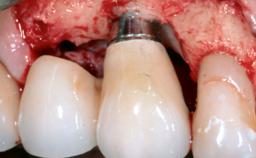

Peripheral Giant-cell Granuloma Associated with Peri-implant Tissues

Giant-cell granulomas (GCG) of the jaws are benign reactive lesions of unknown etiology, unrelated to giant-cell tumors (osteoclastomas), which are defined as benign but locally destructive and aggressive neoplasms (Jundt and coworkers 2005). Depending on their localization at the initial diagnosis, GCG are dived into central (CGCG) and peripheral (PGCG) types. CGCGs occur within the jawbones and appear as unilocular or multilocular radiolucent lesions. The incidence in the general population is very low. They are more commonly found in the mandible, mainly in children and young adults—patients are generally younger than 30 years—and have a greater incidence in females (Heithersay and coworkers 2002). The clinical behavior of CGCGs varies from slowly growing asymptomatic swellings to aggressive lesions that may result in pain, cortical perforation of the affected jaw site, and root resorption (de Lange and coworkers 2007).